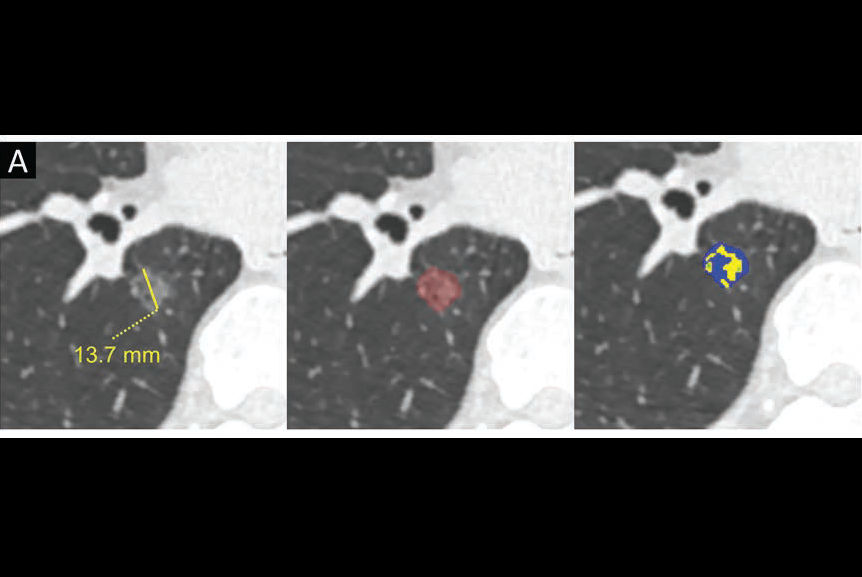

Lung adenocarcinoma is the most common primary lung cancer seen in the U.S. Tumors manifest as ground-glass nodules (GGNs) on CT scans. Deciding whether the lesions are preinvasive, minimally invasive, or invasive, however, is a significant challenge, and these determinations drive the timing of surgery, according to the authors.

To address this challenge, the group developed their deep-learning and radiomics-based approach, which classifies GGNs into preinvasive (atypical adenomatous hyperplasia or adenocarcinoma in situ), minimally invasive, or invasive adenocarcinoma.

In brief, the researchers first constructed three conventional ternary classification models: model 1 was constructed by using a radiomics method; model 2, by a deep-learning method; and model 3, by a joint learning method combining both radiomics and deep learning. The models were progressively modified through framework optimization, joint learning, and an “adjudication strategy,” the authors wrote.